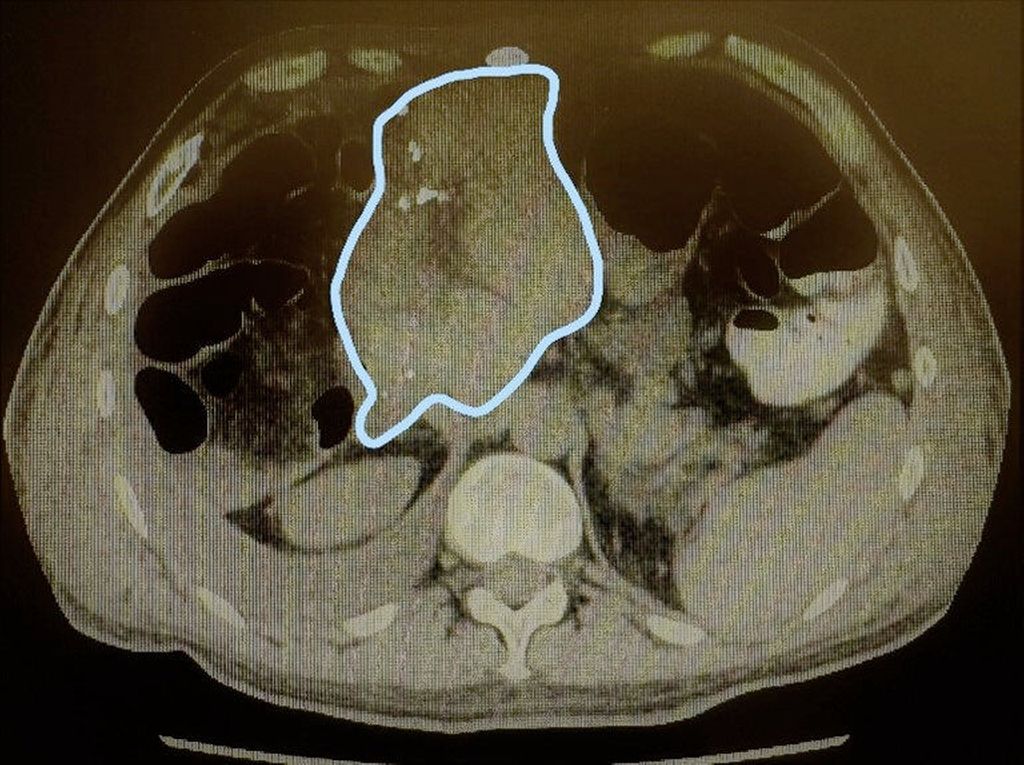

Abb. 2: Große zentrale Metastase eines Rektumkarzinoms (rosa Bereich) sowie sehr kleine linkslaterale Segmente (grüner Bereich)

Abb. 3: Z.n. Resektion i.S. einer erweiterten Hemihepatektomie rechts mit augmentierten linkslateralen Segmenten (blau umrandet)

Welches Verfahren zur Augmentation des FLR genutzt werden sollte, ist aktuell nicht klar festgelegt. Sparrelid E et al. haben die PVE mit dem ALPPS-Verfahren bei kolorektalen Lebermetastasen verglichen und konnten zeigen, dass der Hypertrophieeffekt des ALPPS-Verfahrens (Abb. 2 und Abb. 3) signifikant besser war (66,7% vs. 46,3%; p=0,001).7 Den besten Hypertrophieeffekt hatte jedoch die primäre PVE gepaart mit einer Rescue-ALPPS. Die Rate der erfolgreichen Resektionen war ebenso im ALPPS-Arm höher, jedoch statistisch nicht signifikant (84,5% vs. 73,2%; p=0,08).